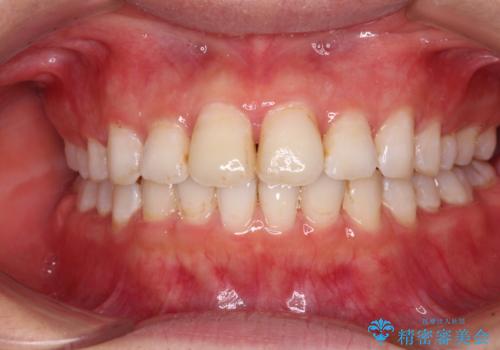

前歯の捻れを改善 インビザラインによる矯正治療

- 前歯の翼状捻転を気にして来院された患者様です。

全体的に叢生は軽度であったため、インビザラインにて矯正治療を行うこととしました。

前歯の幅の大きさも気になっていたため、IPRにより叢生を解消するとともに、歯の大きさも改善しました。